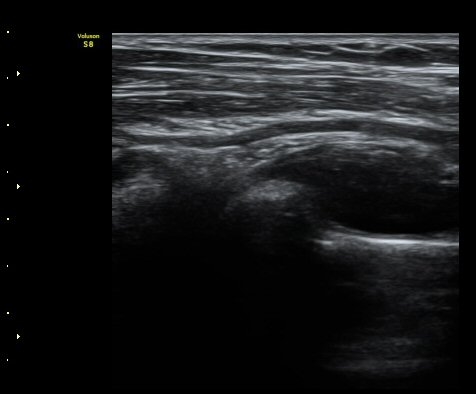

ŽÃËÀÚ¸¦ ¿ä°ñµÎ ºÎÀ§·Î À̵¿ÇÏ´Ï ¿ä°ñµÎ Ç¥Ãþ¿¡ Àú¿¡ÄÚ ³¶Á¾ÀÌ °üÂûµÇ°í ³¶Á¾ÀÇ ¿ÜÃø¿¡¼­

Èİñ°£½Å°æÀÌ ¾Ð¹ÚµÇ°í ÀÖ´Ù(±×¸² 2).

ŽÃËÀÚ¸¦ Á» ´õ ¸»´ÜÀ¸·Î À̵¿ÇÏ´Ï ³¶Á¾Àº ´õ Å©°Ô °üÂûµÈ´Ù(±×¸² 3, 4).